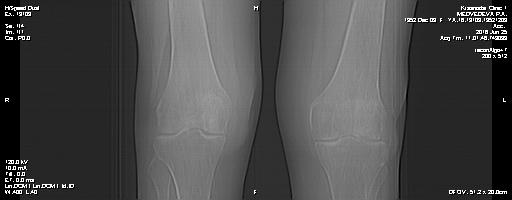

Мне 64 года,житель Краснодара,болят коленные суставы,кисти рук и руки от плеч.Утром не знаю что разминать в первую очередь.Такая скованность.В покое ничего почти не беспокоит.сидя и лежа колени не болят только руки.Хождение по поликлиникам результатов не дает.Да у нас только платные почти клиники и те толком не хотят ничего делать.А в бесплатных даже терапевтов нет (наша 13 пол-ка).Прошу подскажите,как и чем лечить суставы,за 4 года болезни устала от непонятных докторов и их лечения.Пользы нет.